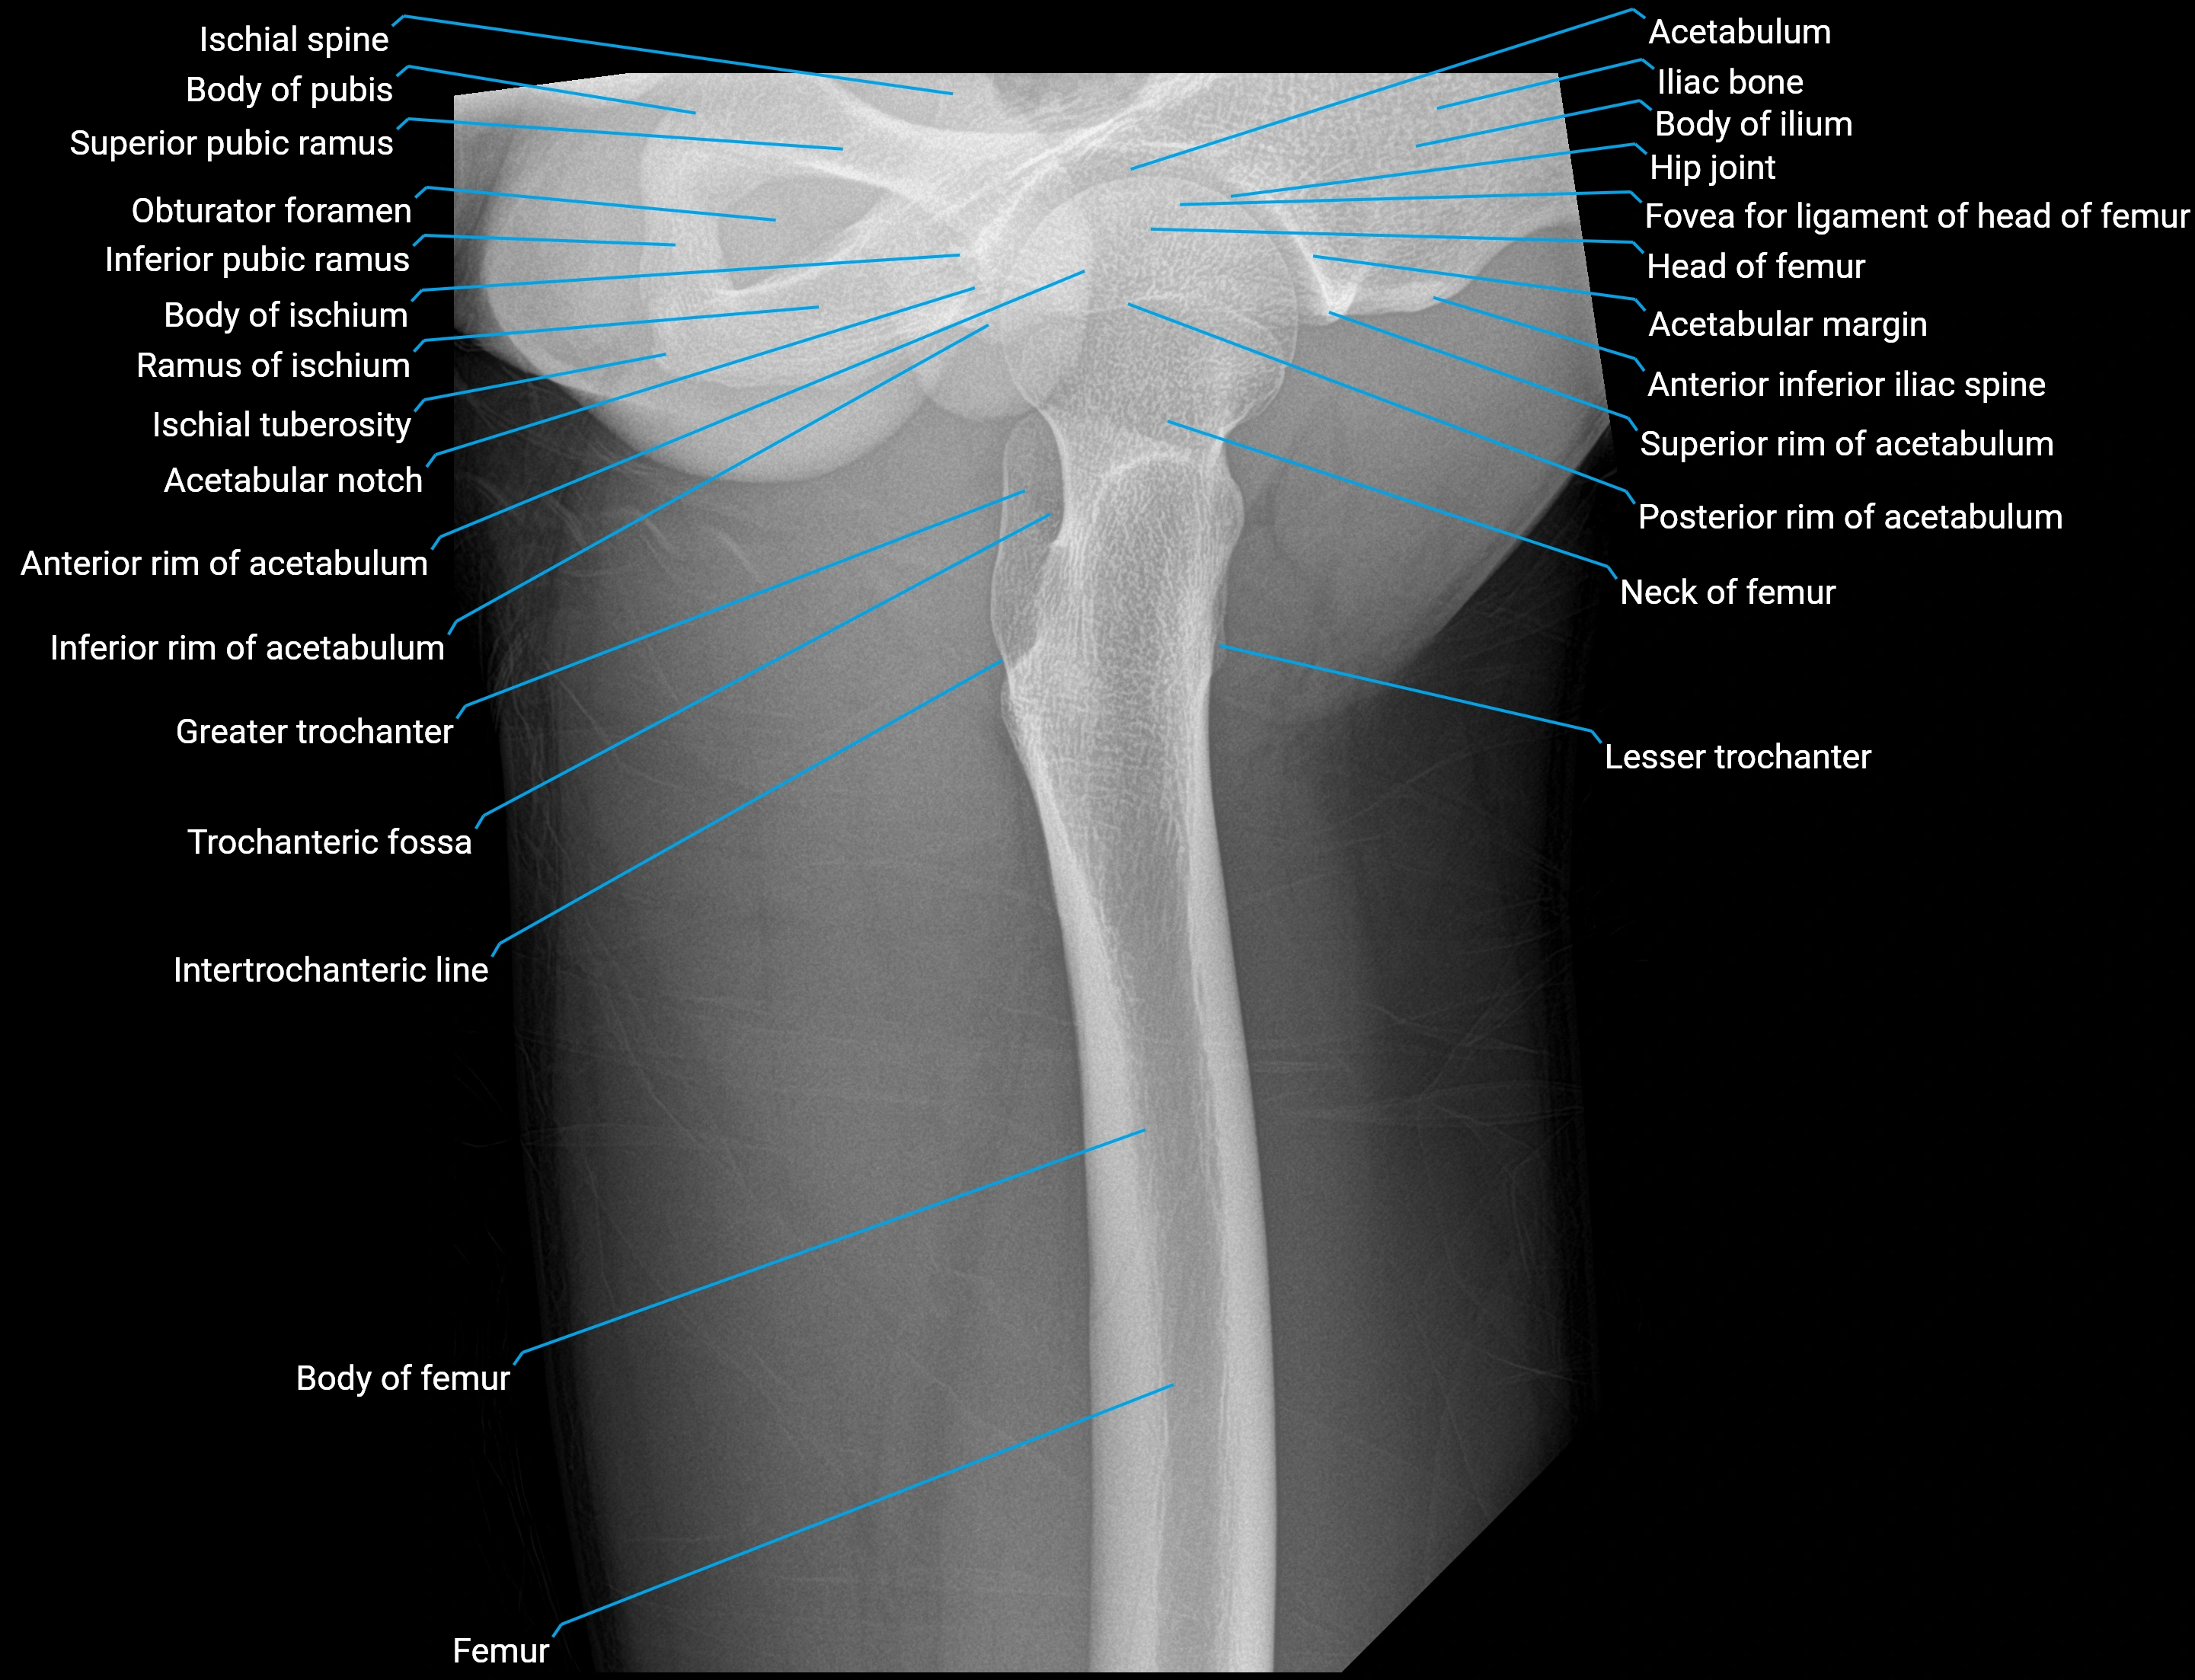

The acetabular labrum is a fibrocartilaginous ring that surrounds the rim of the acetabulum in the hip joint. It deepens the hip socket, increases joint stability, and maintains a suction seal that preserves negative intra-articular pressure. Structurally, the labrum transitions from hyaline cartilage of the acetabulum to dense fibrocartilage at its free edge.

It is triangular in cross-section, with its base attached to the acetabular rim and its apex projecting toward the femoral head. The labrum is most robust superiorly and anteriorly, where load bearing is greatest, and relatively thinner inferiorly.

Structure and Relations

• Superior and anterior labrum: thickest portions, stabilizing against anterior dislocation

• Inferior labrum: blends with the transverse acetabular ligament bridging the acetabular notch